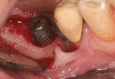

Peri-implant inflammations represent serious diseases after dental implant treatment, which affect both the surrounding hard and soft tissue. Due to prevalence rates up to 56%, peri-implantitis can lead to the loss of the implant without multilateral prevention and therapy concepts. Specific continuous check-ups with evaluation and elimination of risk factors (e.g. smoking, systemic diseases and periodontitis) are effective precautions. In addition to aspects of osseointegration, type and structure of the implant surface are of importance. For the treatment of peri-implant disease various conservative and surgical approaches are available. Mucositis and moderate forms of peri-implantitis can obviously be treated effectively using conservative methods. These include the utilization of different manual ablations, laser-supported systems as well as photodynamic therapy, which may be extended by local or systemic antibiotics. It is possible to regain osseointegration. In cases with advanced peri-implantitis surgical therapies are more effective than conservative approaches. Depending on the configuration of the defects, resective surgery can be carried out for elimination of peri-implant lesions, whereas regenerative therapies may be applicable for defect filling. The cumulative interceptive supportive therapy (CIST) protocol serves as guidance for the treatment of the peri-implantitis. The aim of this review is to provide an overview about current data and to give advices regarding diagnosis, prevention and treatment of peri-implant disease for practitioners.